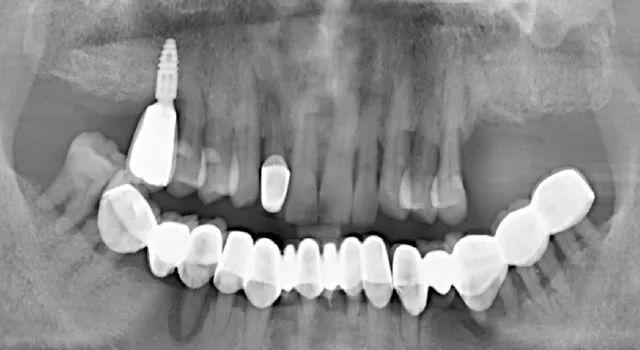

無(wú)獨(dú)有偶,一起看看那些價(jià)格便宜但醫(yī)療質(zhì)量不過(guò)關(guān)的種植牙:劣質(zhì)種植體導(dǎo)致的種植牙失敗

手術(shù)失敗的種植牙,使用壽命僅僅只有2個(gè)月(種植窩空虛,頰側(cè)嵴頂骨缺損)